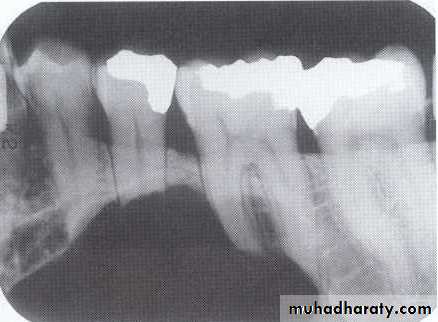

Increased secretion of parathormone, causes generalized skeletal bone resorption leading to osteopenia (generalized decrease in bone density).Single or multiple radiolucency in the maxilla & mandible.

• Loss of normal bone trabeculation & replaced by fine poorly calcified bone spicules that give ground glass appearance.

• Missing of lamina dura.

Loss of the lamina dura and the granular texture of the bone pattern.